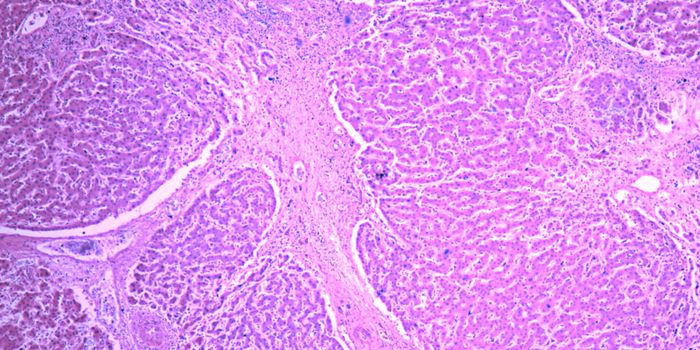

MAR 17, 2015CancerVanderbilt University researchers have achieved the first "image fusion" of mass spectrometry and microscopy - a technic ...

NOV 16, 2019CancerNew research published in the journal Gastroenterology offers insight on gastric cancer and the presence of the common b ...